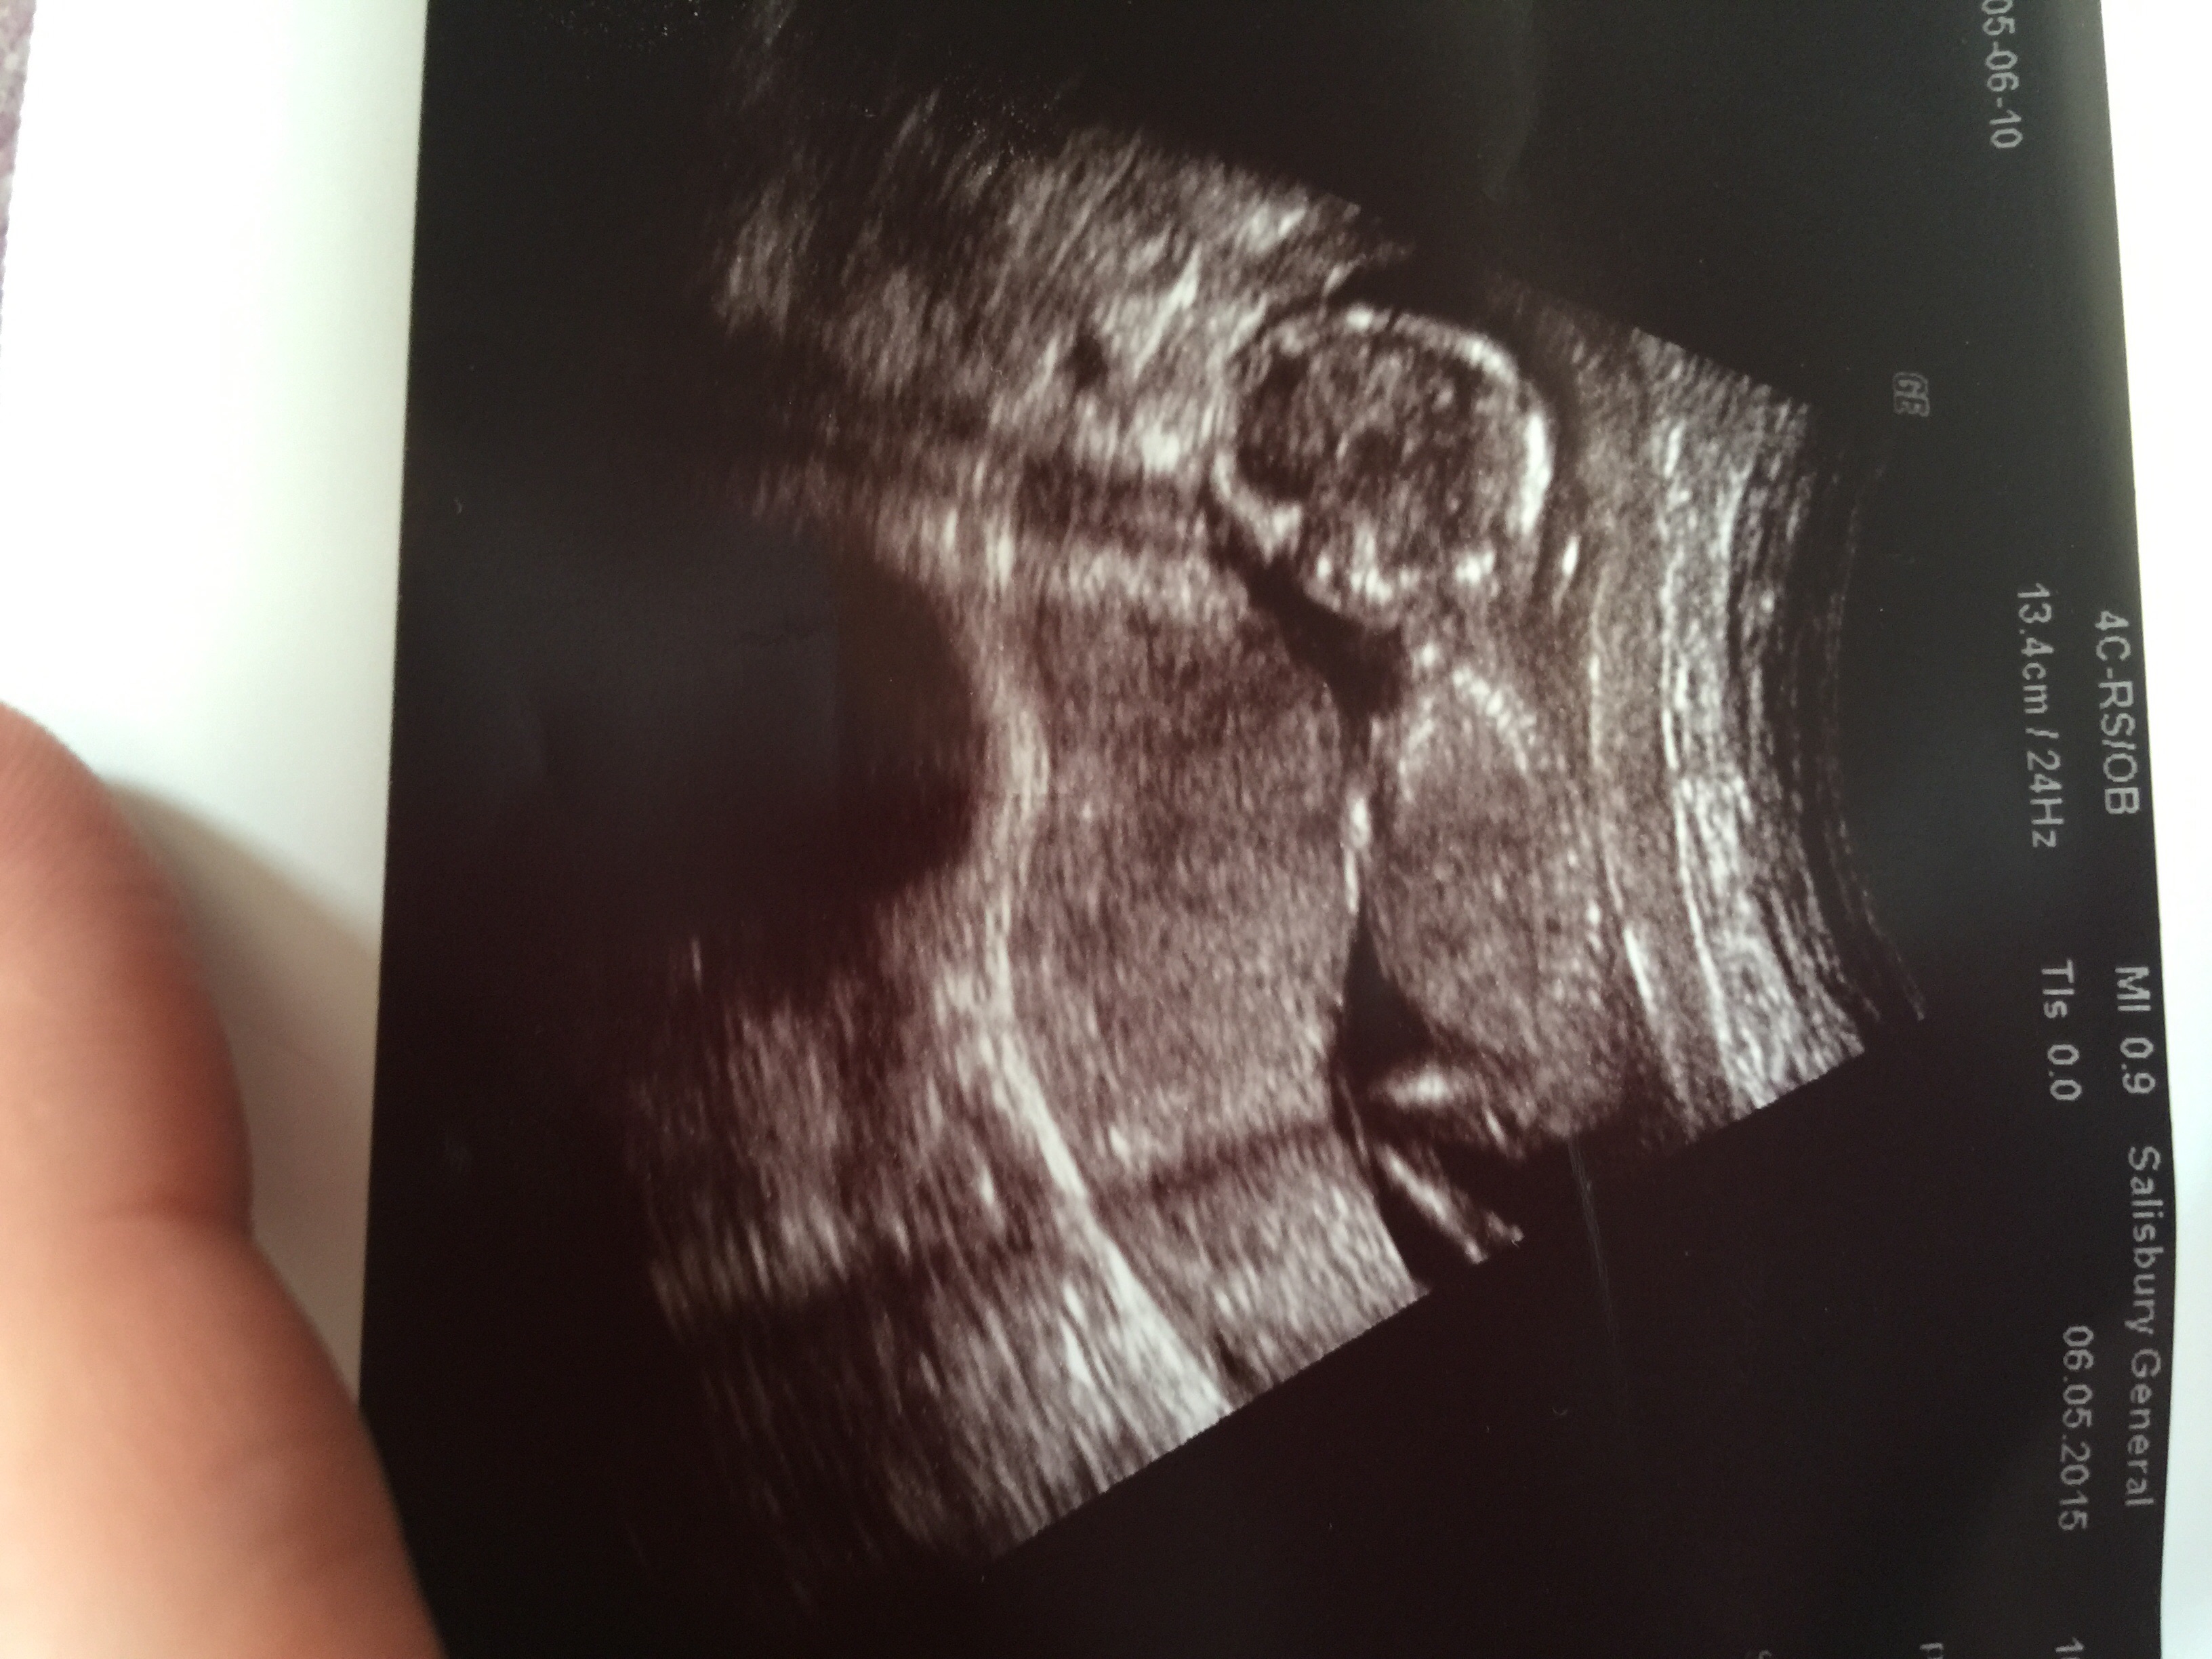

Hope it's okay to post my scan picture up here. I was just wondering if anyone has any thoughts as to what baby may be, boy or girl? It was taken at 14+1 and I would love to know, I find it fascinating how anyone can tell anything on these pictures lol!